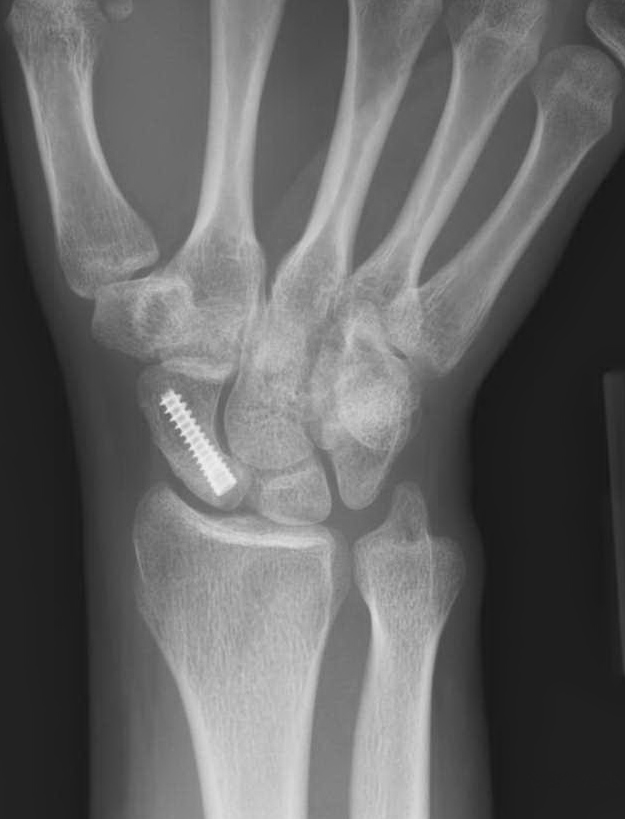

Scaphoid ORIF